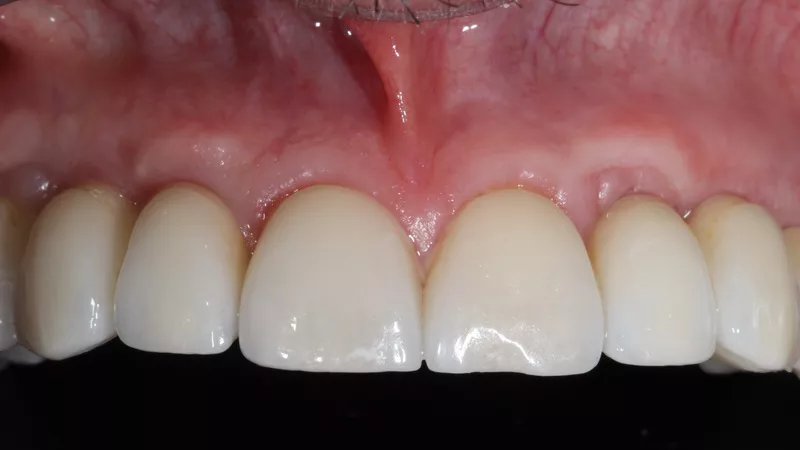

16a-b. Final situation after inserting bridges to 15 Ncm, cementing the crown to tooth 15, and gluing the veneers to teeth 11 and 21.

16c. 4 years post implant placement.

18. Situation 4 years post implant placement.